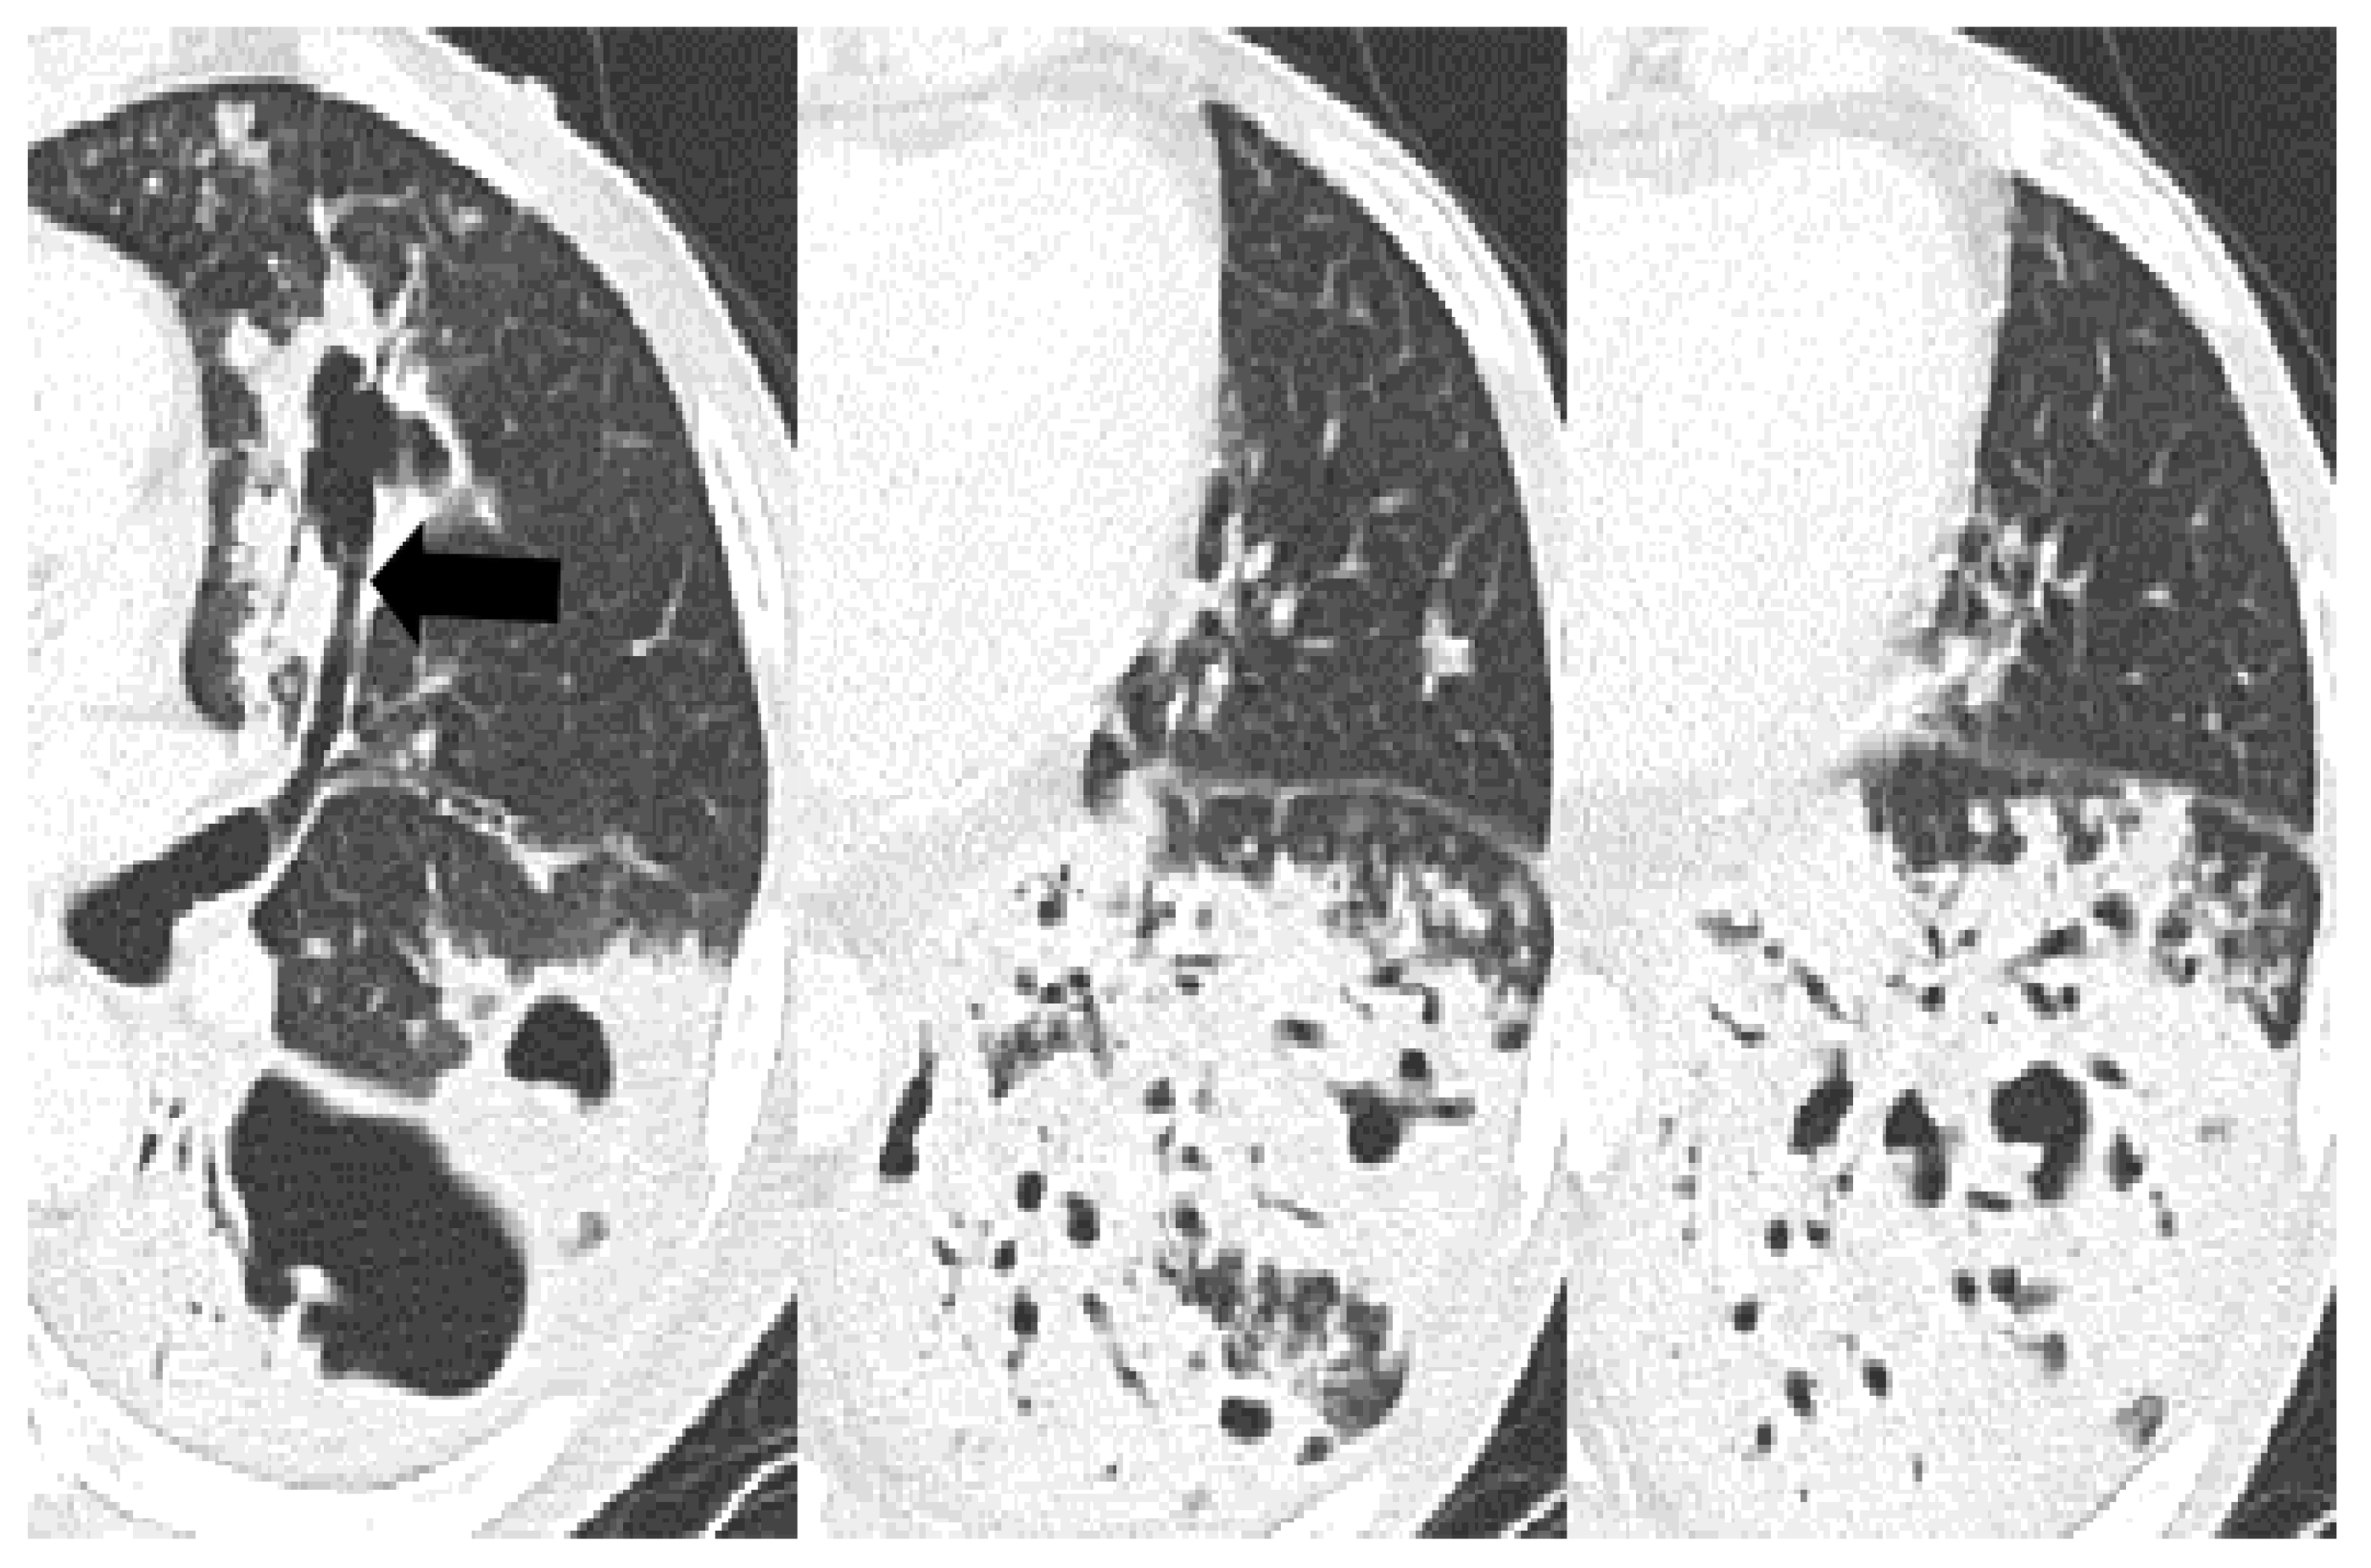

| Bronchial erosion | 157 (47) | 110 (44) | 9 (30) | 38 (73) | <0.001 | 0.157 | <0.001 | <0.001 |

| Cavitation | 157 (47) | 109 (43) | 7 (23) | 41 (79) | <0.001 | 0.038 | <0.001 | <0.001 |

| Tree-in-bud | 134 (40) | 98 (39) | 12 (40) | 24 (46) | 0.610 † | 0.893 | 0.32 | 0.589 |

| Bronchovascular bundle thickening | 249 (74) | 184 (73) | 21 (70) | 44 (85) | 0.172 | 0.752 | 0.072 | 0.116 |